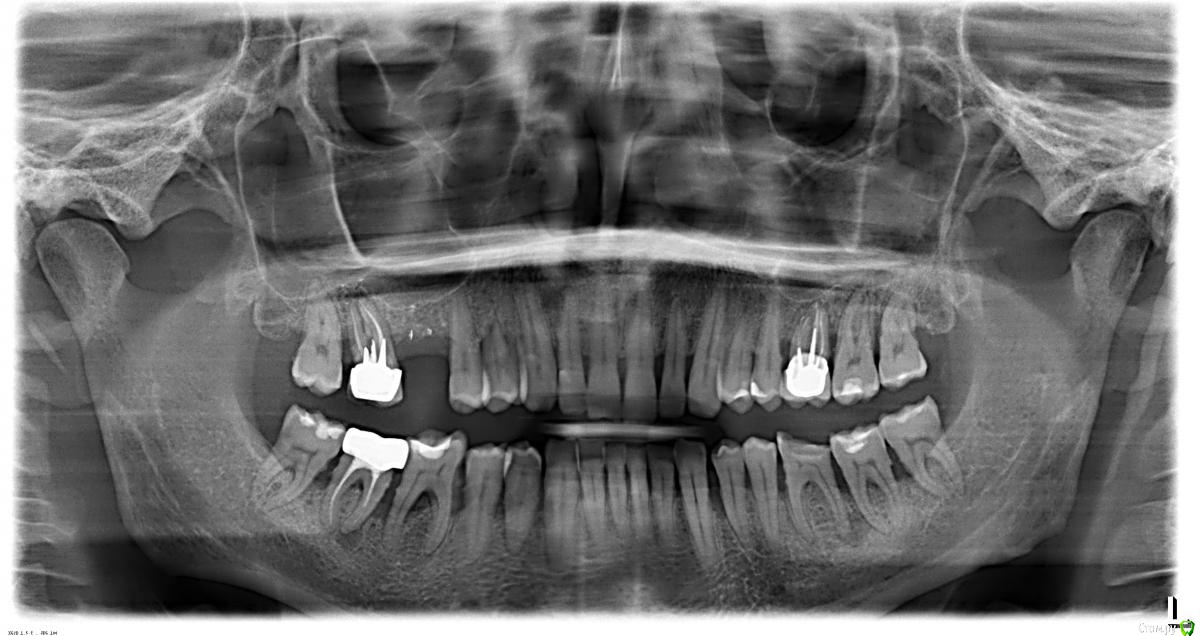

ОПТГ во вложении.

В настоящее время прогрессирующее ухудшение состояния десен, подвижность зубов 2 степени, пародонтологические карманы 5-7 мм. Кроме этого под №36 образовалась киста со свищем в десне. Также имеются зубы с плохо пролеченными каналами: №17 и 46.

1,5 года назад потерял 16 зуб после "флюса".